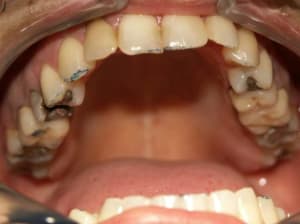

Cas_4_b_a1uady.jpg

Voir le message contenant cette image